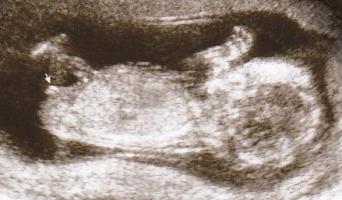

وهاذي صورة البنت

وشوفي عضوها موازي للعمود الفقري وهاذا الي بيكون البضر

شفتي كيف الفرق بسيييييييييييييط